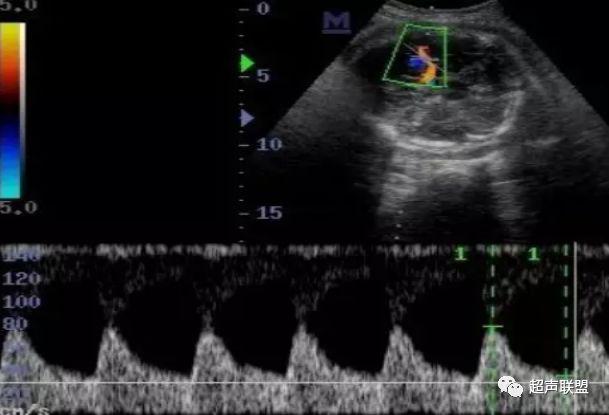

2 胎儿大脑中动脉测定

缺氧早期大脑血液供应增加,颅内血管扩张,阻力降低,舒张末期血流速度增加,PI、RI值下降,说明缺氧早期的血流再分配。当大脑中动脉RI、PI值明显下降,而脐动脉和腹主动脉的PI值升高,大脑中动脉PI值与脐动脉PI值的比值低于2个标准差时,提示严重缺氧的存在。

1、比值标准:大脑中动脉阻力降低,妊娠期,大脑中动脉RI <脐动脉RI;

4、当大脑中动脉RI及PI值明显下降,而脐动脉及腹主动脉的PI值之间升高,大脑中动脉PI值与脐动脉PI值低于两个标准差时,提示为胎儿严重缺氧;

图3 正常大脑中动脉血流频谱

图4 大脑中动脉血流阻力减低